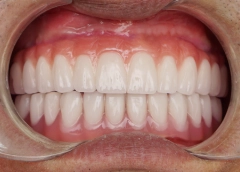

• Tình trạng răng trước đây:Mất hết răng cả 2 hàm, tiêu xương hàm

• Bác sĩ chỉ định:Cấy ghép Implant All On 4

• Implant sử dụng:Implant Mis C1 Đức

• Răng sứ sử dụng:Răng sứ Titan Mỹ

Từ đó, chú Hải đã quyết định sẽ thực hiện Implant tại I-Dent. Bởi chú nhận ra chất lượng quan trọng hơn chi phí rất nhiều, và kết quả trồng răng cuối cùng đã không phụ lòng mong đợi của chú.

Chú Hải có được hàm răng mới chắc khỏe, ăn uống thoải mái mà không phải kiêng cữ như trước. Nhờ đó mà sức khỏe ngày càng tốt hơn, chú cũng thêm vui vẻ, yêu đời.